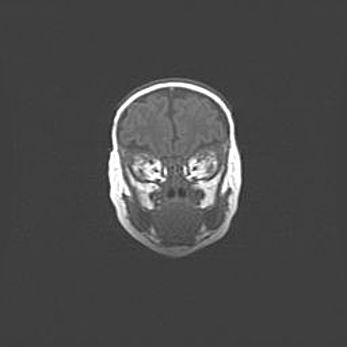

Наружная гидроцефалия с возможной атрофией височных областей.

Возраст: 28 дней

Вес: 3670 г

Пол: мужской

Окружность головы: 38 см

Срок гестации: 40 недель

Гидроцефалия головного мозга у новорожденных – это заболевание, которое характеризуется скоплением избыточного количества спинномозговой жидкости в желудочковой системе головного мозга в результате затруднения её перемещения от места выработки к месту поглощения в кровеносную систему или вследствие нарушения абсорбции. При открытой наружной форме гидроцефалии у новорожденных расширяются и переполняются субарахноидные пространства.

При нормотензивных  формах,  которые,  как  правило,  являются  следствием  перенесенных ишемических  повреждений  паренхимы  мозга,  возможно  сочетание микроцефалии  с нормотензивной гидроцефалией. В основе данных изменений лежит атрофия больших полушарий с преимущественной  локализацией  в  лобно-височных  областях.